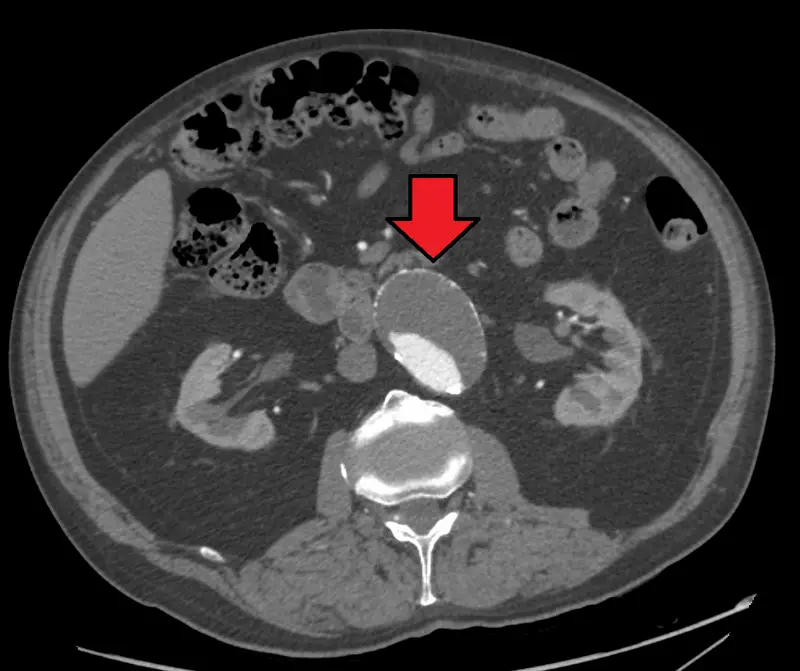

Abdominal Aortic Aneurysm

Abdominal aortic aneurysm (AAA) is an aneurysm of the abdominal aorta.

Abdominal aortic aneurysm typically develops above the aortic bifurcation but below the renal arteries.

Abdominal aortic aneurysm (AAA) is typically associated with hypertension and atherosclerosis.

- Atherosclerosis

Atherosclerosis causes the vessel wall to atrophy and become weaker by raising the diffusion barrier to the media.

Complications of abdominal aortic aneurysm (AAA) include:

- Rupture, especially when the diameter is greater than 5 cm

- Compression of nearby structures (such as the ureter)

- Thrombosis

- Embolism